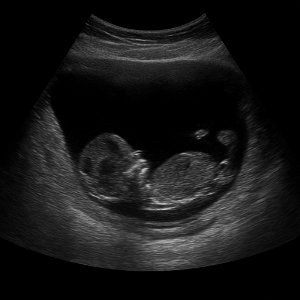

임산부나 어린이도 검사 가능한가요?

네, 복부초음파는 방사선을 안 쓰고 안전하게 장기를 들여다보는 방법이어서 임산부나 태아, 그리고 어린이까지 모두 받을 수 있어요 . 특히, 산과 초음파(태아 초음파)는 매우 일반적이며 안전한 검사로 자리 잡았어요 .